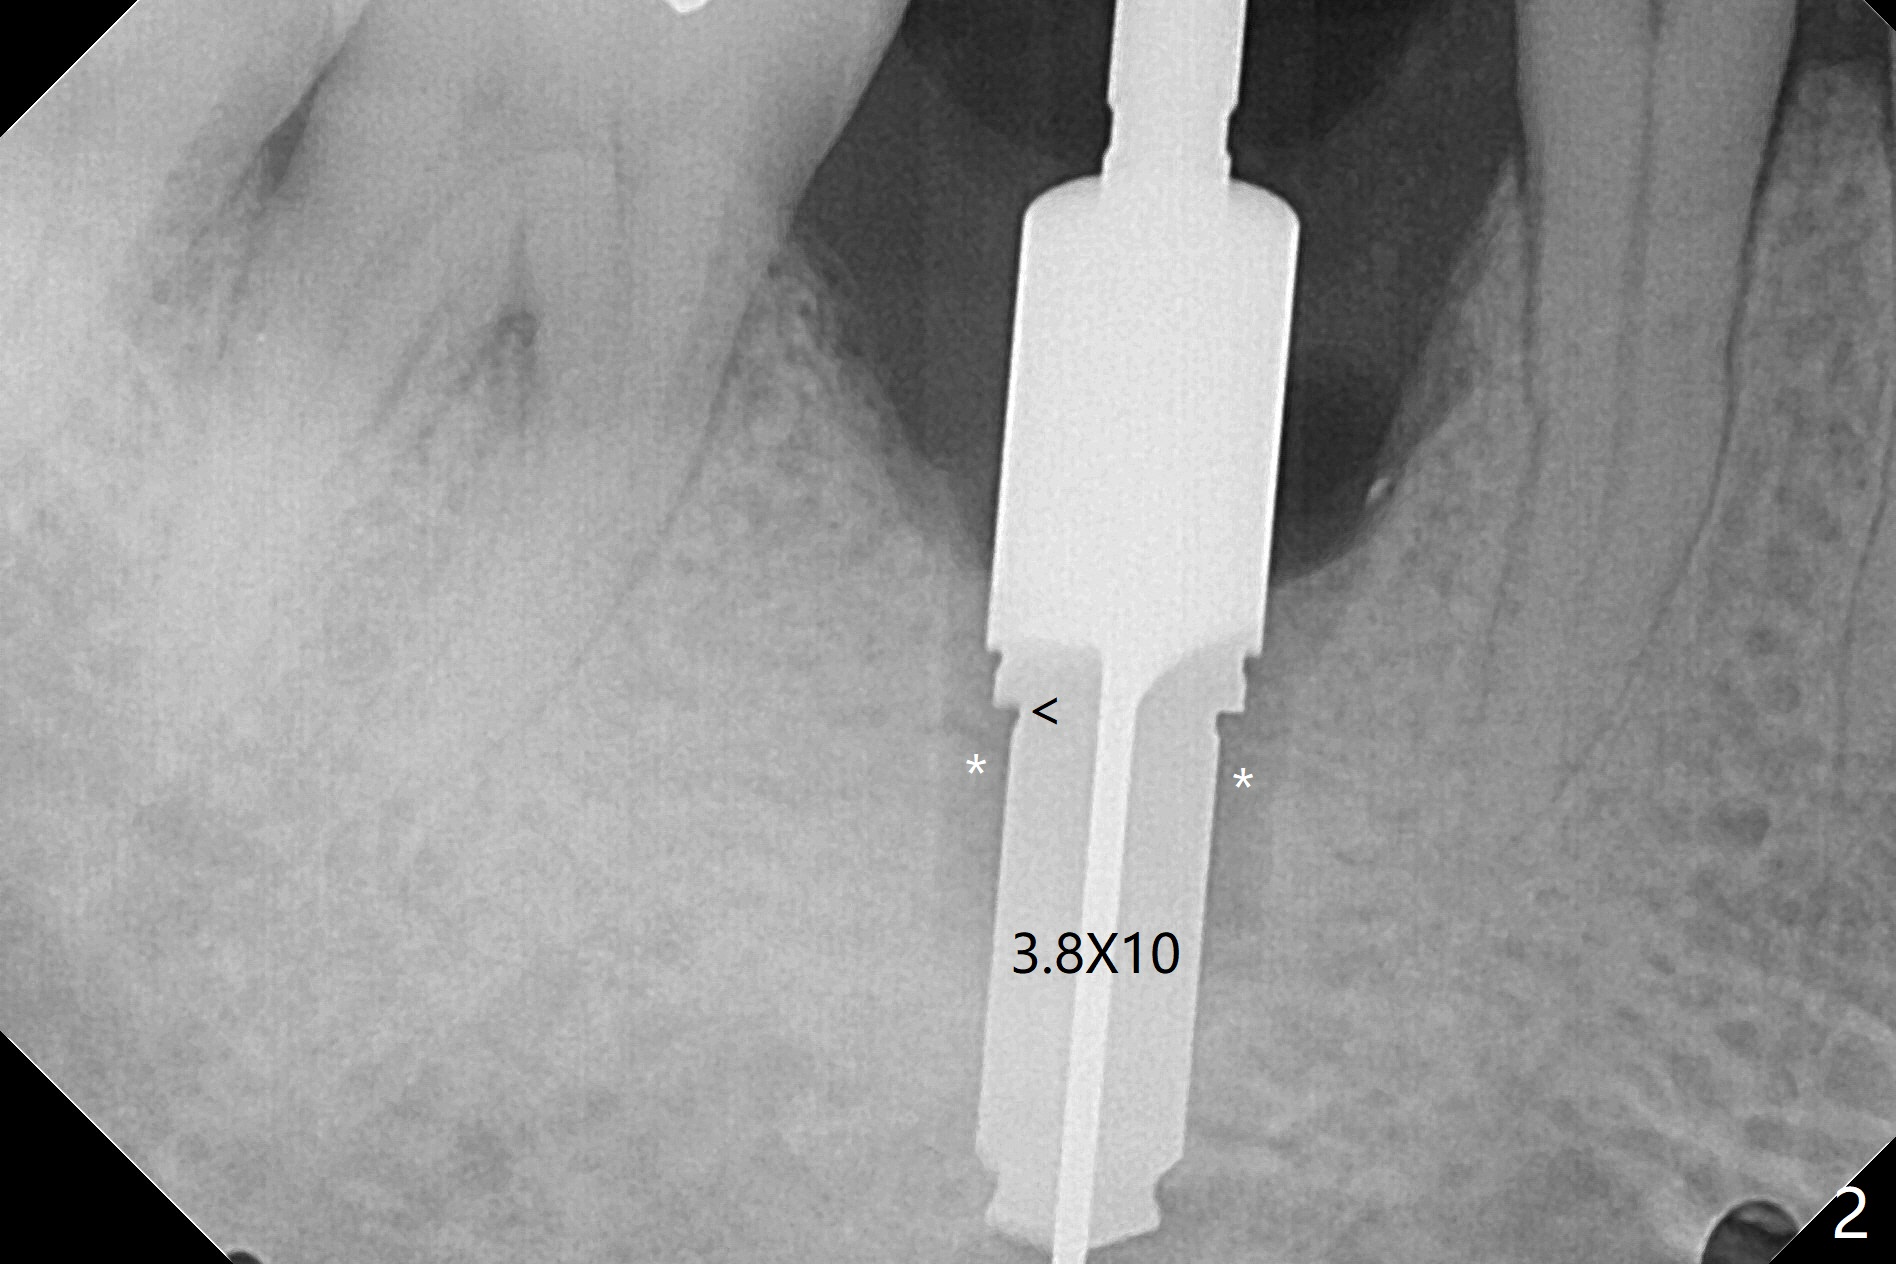

When the woman with periimplantitis at #30 returns to clinic, the abutment is found to be fractured (Fig.1 *) and difficult to remove. After implant removal with trephine burs, osteotomy is initiated lingual (Fig.2). A smaller and shorter implant (4.5x11.5 vs. 5.0x13 mm previously) is placed deeper (Fig.3) so that there is space for sticky bone buccal and coronal (Fig.4 *, 5 (postop reanalysis of preop CT)). After placement of 2 pieces of PRF membranes, the wound is closed with 4/0 PGA. The buccal flap is perforated due to periimplantitis and surgical manipulation. Periodontal dressing is applied.